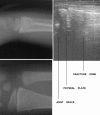

Objective: The management and the diagnostic modalities used in cases of undisplaced greenstick and torus fractures of the distal radius in children vary between different treatment centres. The aim of this study was twofold: firstly, to analyse the sensitivity of X-rays versus ultrasound to diagnose these fractures; secondly, to compare three available treatment options (plaster cast, Futuro splints, and double Tubigrip) in terms of pain, analgesia requirements, grip strength, deformity, stiffness and interference with a child's activities of daily living.

Results: In terms of diagnosis, the ultrasound was found to be more sensitive than X-rays for diagnosing these fractures. Our results also showed that Tubigrip was superior in terms of interference with a child's ADLs, stiffness and grip strength. However, there was no difference in the levels of pain, analgesia required, and deformity.

Conclusion: These results support the idea that ultrasound is an effective and sensitive tool for detecting undisplaced greenstick and torus fractures of the distal radius in children. Treating these fractures with functional nonrigid devices (Tubigrip) results in improved function without increased discomfort or deformity.